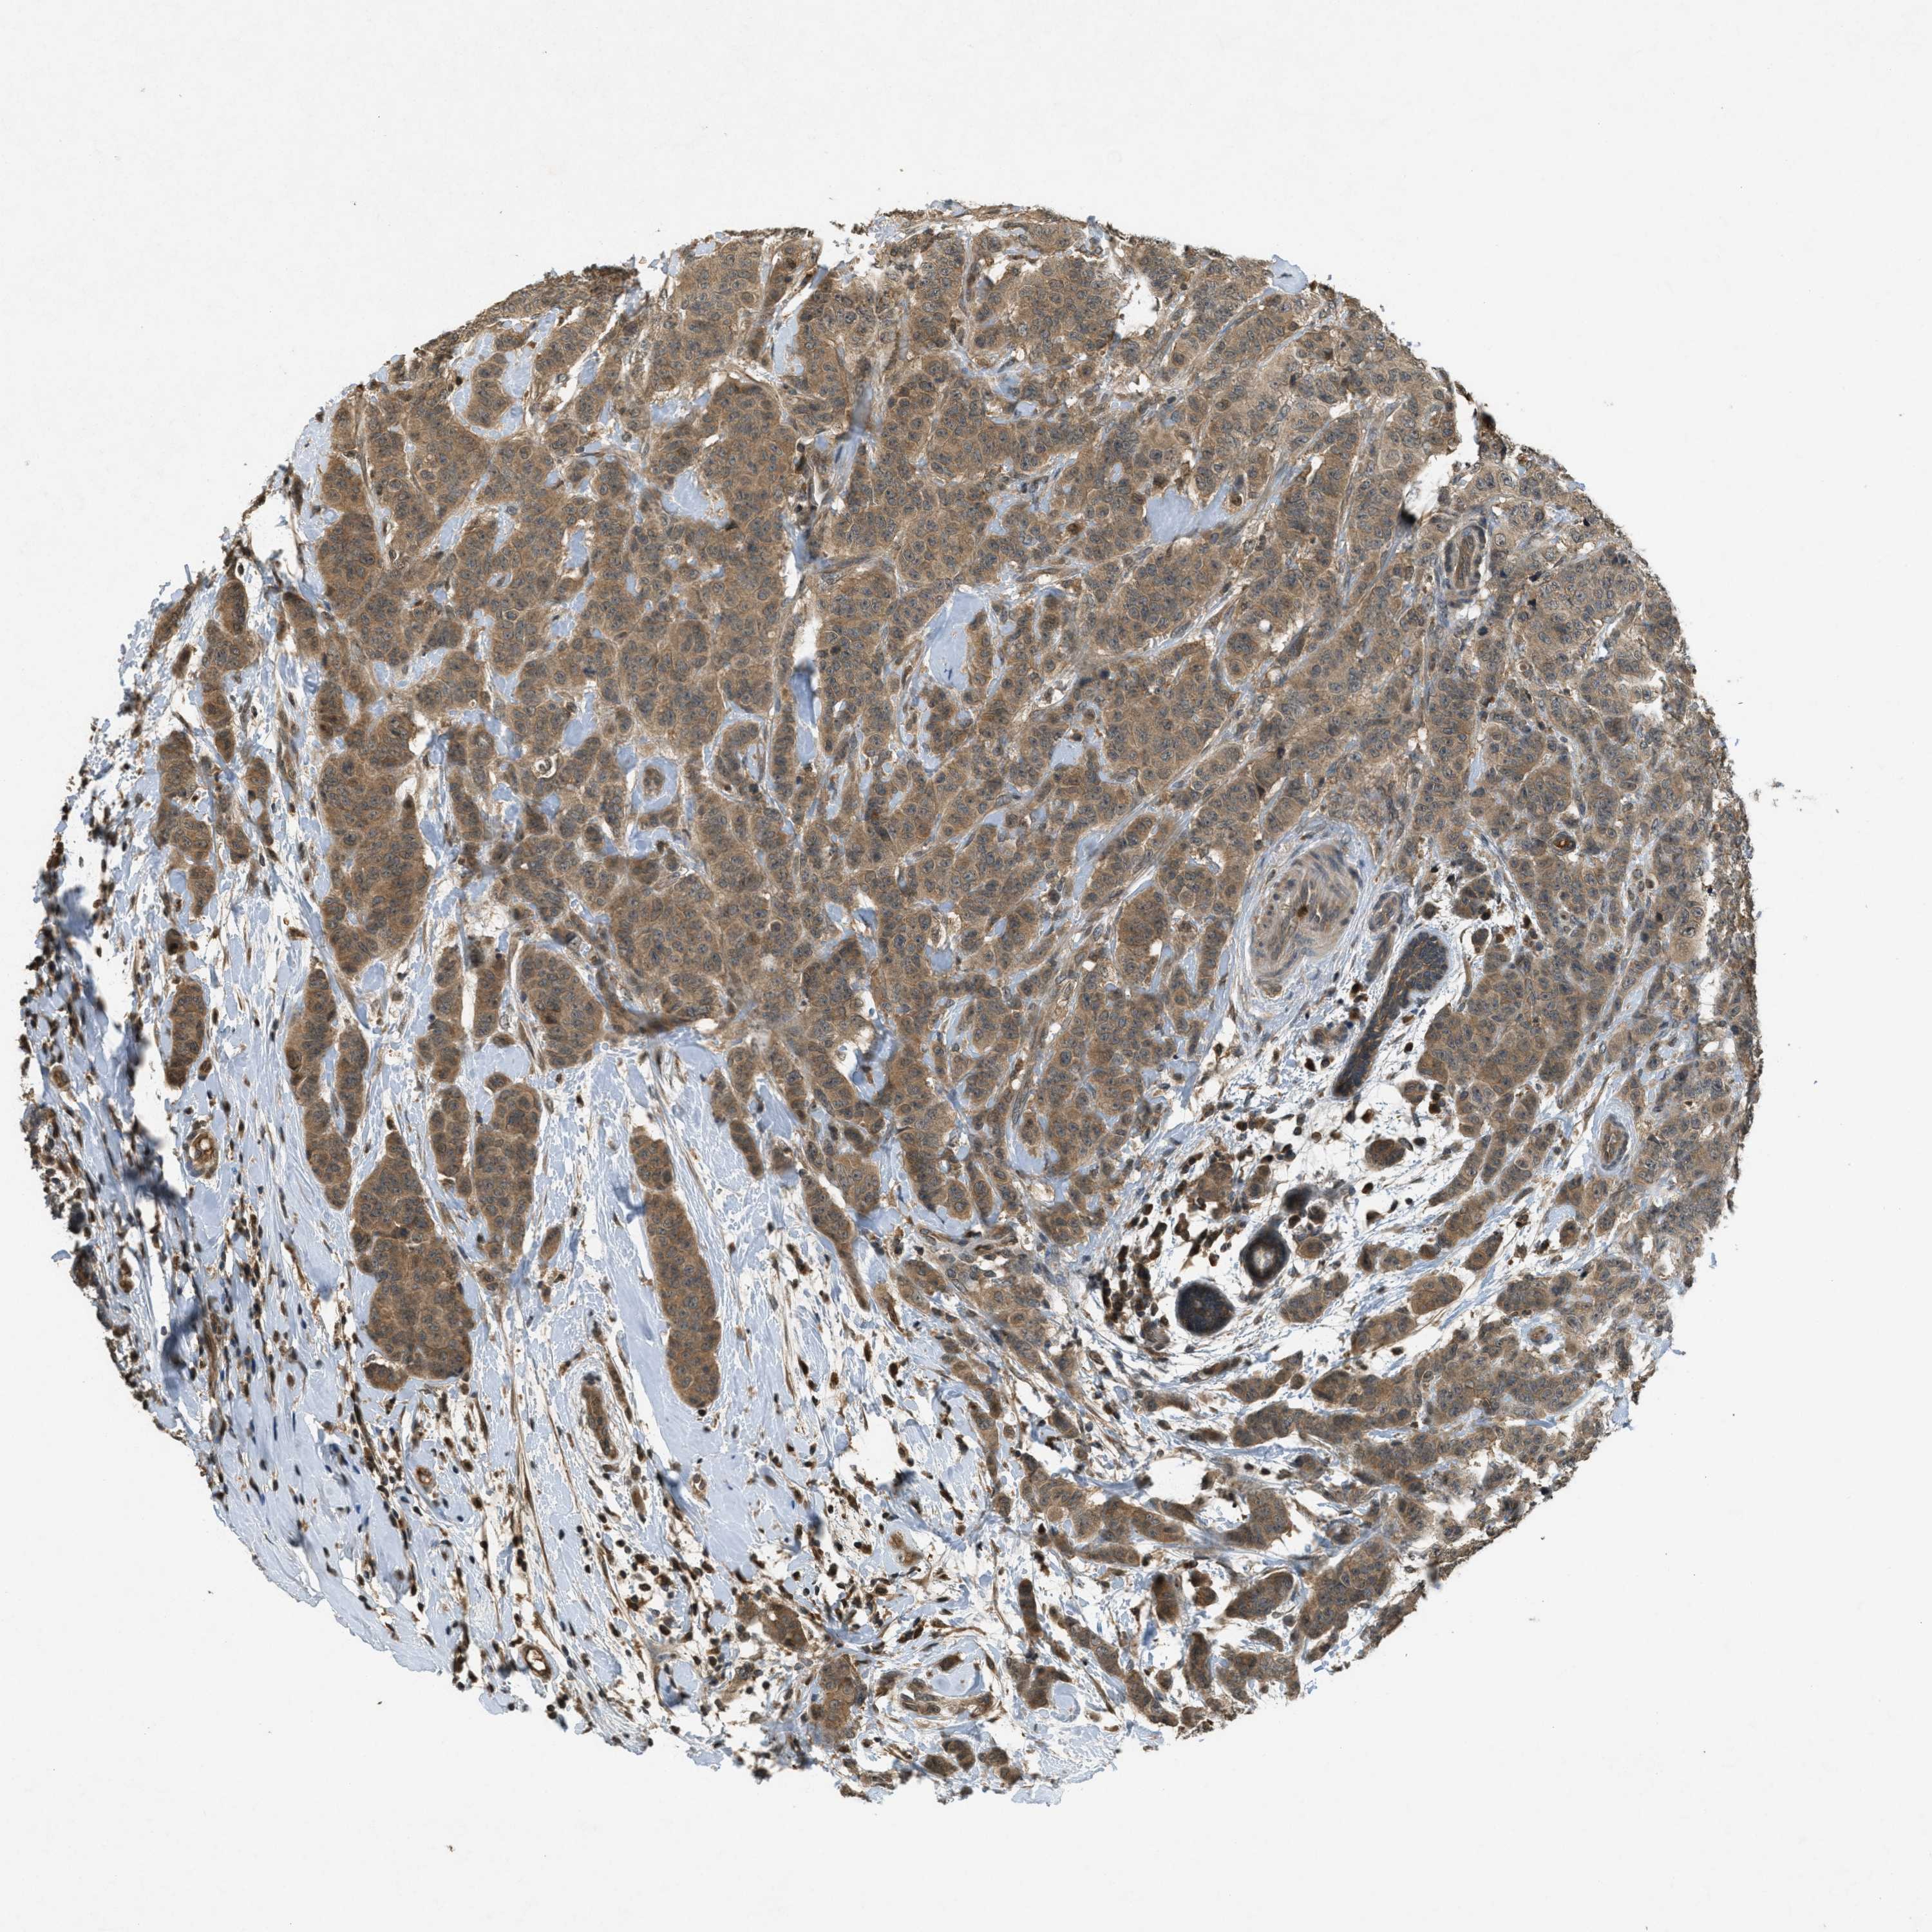

BRCA TCGA BRCA VALIDATION PROTEIN EXPRESSION